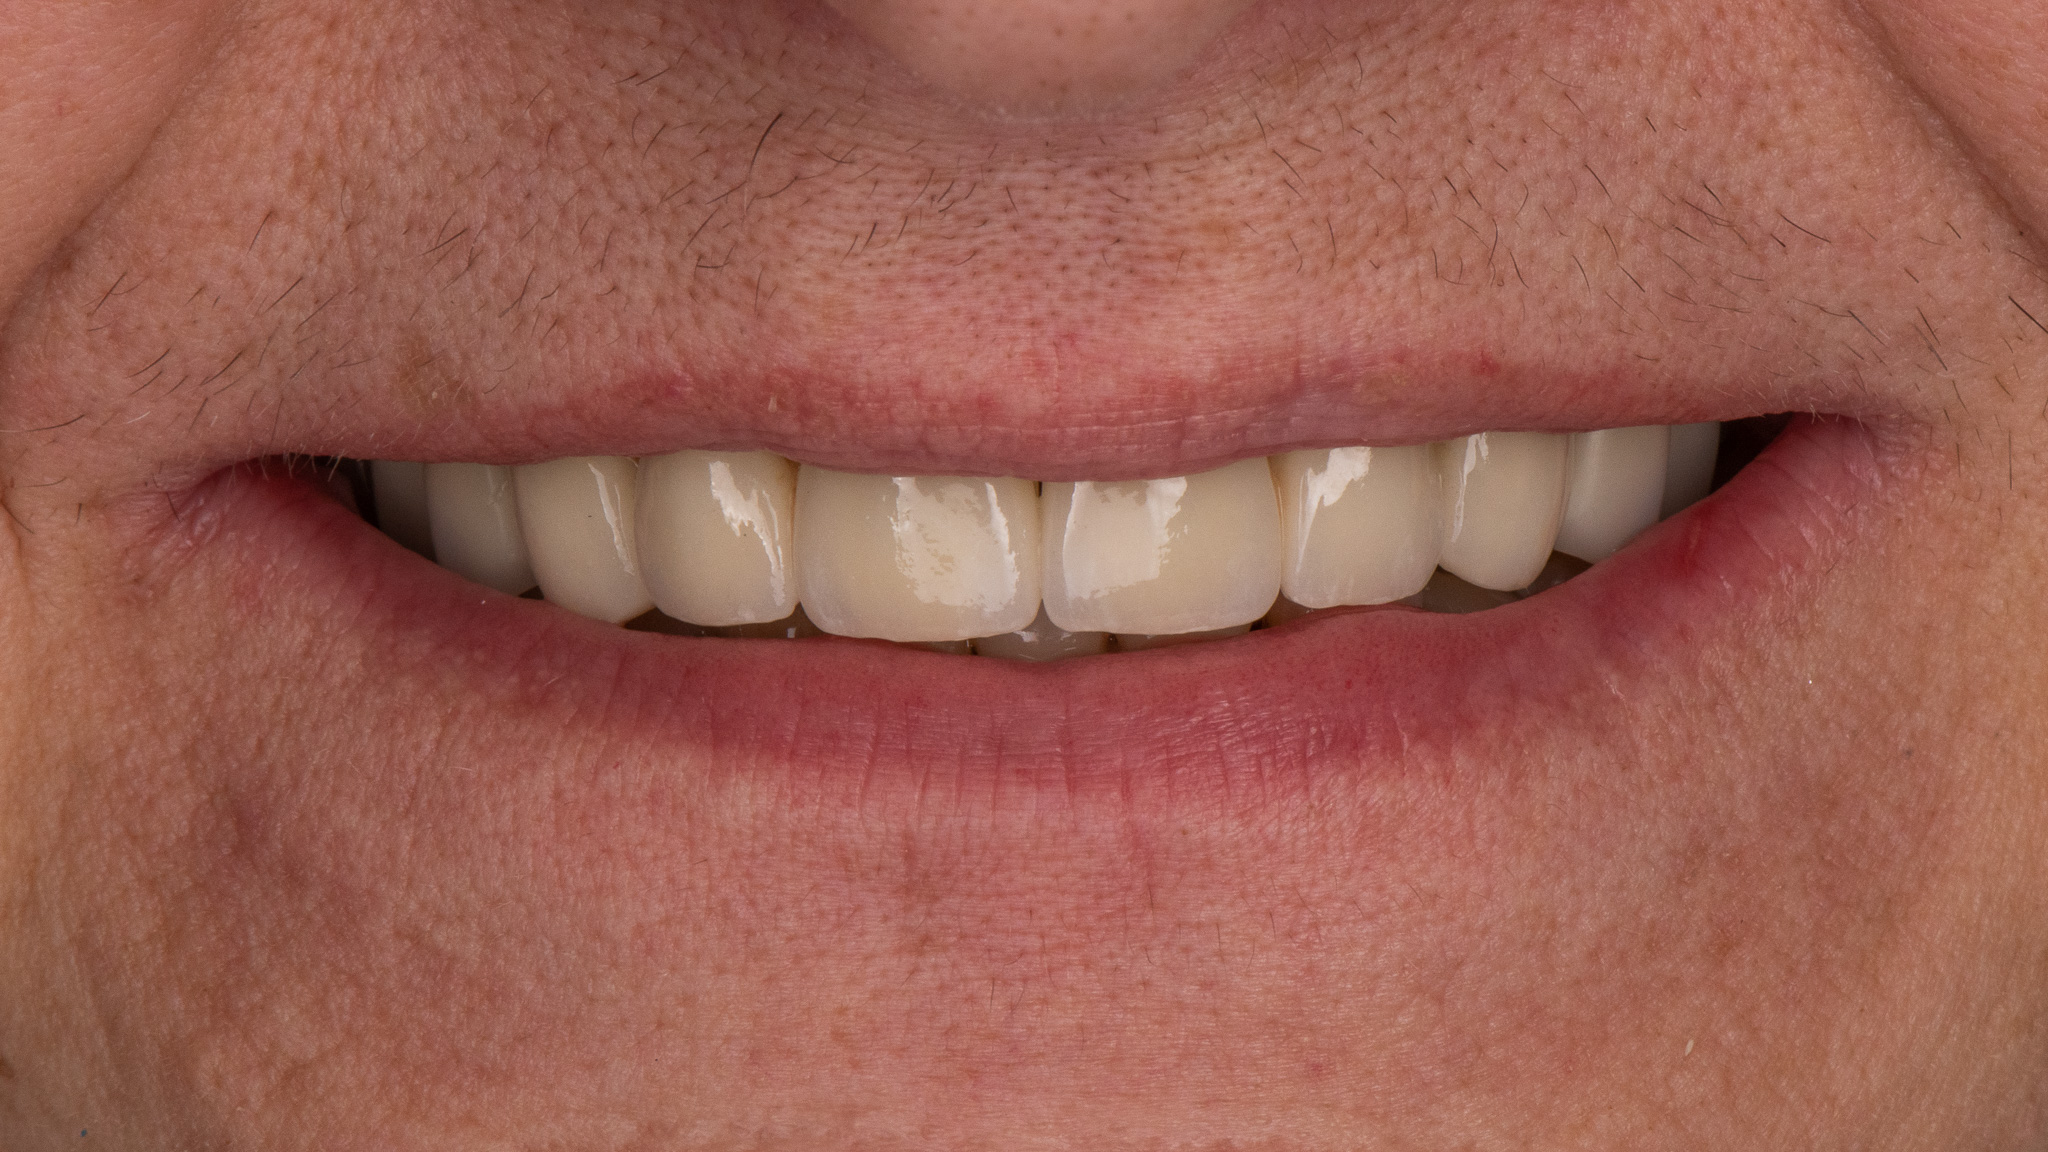

Pacjent zgłosił się w celu poprawy estetyki uzębienia, oraz wymiany użytkowanego od lat mostu protetycznego

Zaplanowane leczenie obejmowało wykonanie nowych koron pełnoceramicznych na podbudowie cyrkonowej na zęby górne oraz bezklamrowej protezy szkieletowe na zatrzaskach - rozwiązanie zapewniające wysoki komfort żucia oraz estetykę uśmiechu - brak widocznych elementów protezy na zębach własnych pacjenta.